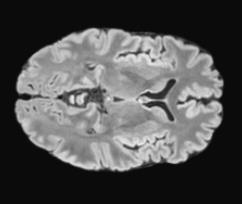

We propose a parameter efficient Bayesian layer for hierarchical convolutional Gaussian Processes that incorporates Gaussian Processes operating in Wasserstein-2 space to reliably propagate uncertainty. This directly replaces convolving Gaussian Processes with a distance-preserving affine operator on distributions. Our experiments on brain tissue-segmentation show that the resulting architecture approaches the performance of well-established deterministic segmentation algorithms (U-Net), which has never been achieved with previous hierarchical Gaussian Processes. Moreover, by applying the same segmentation model to out-of-distribution data (i.e., images with pathology such as brain tumors), we show that our uncertainty estimates result in out-of-distribution detection that outperforms the capabilities of previous Bayesian networks and reconstruction-based approaches that learn normative distributions.